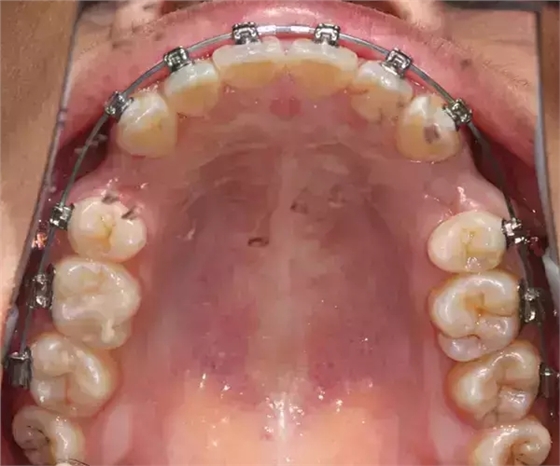

患者側(cè)面凸,鼻唇角較銳,笑時(shí)露齦笑明顯上下牙列擁擠,磨牙尖牙Ⅱ 類關(guān)系,3 度的深覆牙合,上頜中切牙伸長內(nèi)傾拔除上頜雙側(cè)的第一前磨牙,先粘上頜高轉(zhuǎn)矩的自鎖托槽排齊牙列,唇向開展上頜切牙,有一定的覆蓋,粘下頜標(biāo)準(zhǔn)轉(zhuǎn)矩托槽,上頜 1, 2 之間植入種植支抗壓入,同時(shí)后牙 5, 6 之間植入種植支抗內(nèi)收前牙,打開咬合關(guān)閉間隙。治療關(guān)鍵:前牙轉(zhuǎn)矩的控制第 1 個(gè)月 上頜粘上 Damon Q 高轉(zhuǎn)矩托槽,上 .014 熱激活 NiTi 絲。第 3 個(gè)月 上換 .014 x .025 熱激活 NiTi 絲。第 5 個(gè)月 上頜基本排齊,覆蓋增大,上換 .017 x .025 NiTi絲,下頜粘托槽,下 .014 熱激活 NiTi 絲。第 7 個(gè)月 上 .017 x .025 NiTi 絲加搖椅,下?lián)Q .014 x .025 熱激活 NiTi 絲第 9 個(gè)月 上頜換 .019 x .025 NiTi 絲加搖椅,下頜換 .017 x .025 NiTi 絲第 11 個(gè)月 下頜換 .019 x .025 加搖椅,上頜 1, 2 之間, 5, 6 之間植入種植釘,下頜出現(xiàn)散隙。第 13 個(gè)月 上頜換 .019 x .025ss 加搖椅,前牙種植釘用 Power Chain 壓低前牙(每側(cè) 100g),后牙種植釘關(guān)閉間隙(每側(cè) 150g),下?lián)Q .019 x .025ss,Power Chain 關(guān)閉間隙。第 19 個(gè)月 上頜前牙基本壓低到位去除前牙種植釘,繼續(xù)用關(guān)閉間隙,下頜散隙關(guān)閉。

第 22 個(gè)月 上頜覆蓋變小,去除 5, 6 之間種植釘,后牙前移關(guān)閉間隙。第 30 個(gè)月 患者未配合中線牽引,下中線仍有 1mm 右偏,患者對矯治效果滿意要求拆除,拆除固定矯治器,取模制作壓模保持器。 1.骨性 Ⅱ 類的患者內(nèi)收前牙時(shí)需對上頜前牙的轉(zhuǎn)矩進(jìn)行較好的控制才能獲得良好的面型和唇部形態(tài)。 2.露齦笑的患者治療前要分析其病因是唇、牙齦、牙齒、牙槽骨、上頜骨或多種因素結(jié)合,再制定矯治方案。 3.Ⅱ 類第二分類伴露齦笑的患者的上頜前牙移動軌跡是唇向開展-壓低-整體內(nèi)收。 4.Ⅱ 類第二分類牙齒舌傾比較厲害的情況,上頜中切牙慎用樹脂咬合墊。 5.壓低前牙或控根移動時(shí)容易發(fā)生牙根的吸收,需輕力緩慢的移動。